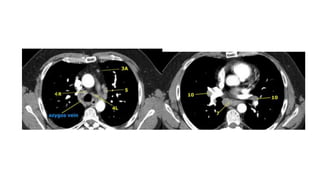

Localize within Mediastinum

Mediastinal Lines

Mediastinal Lymphadenopathy